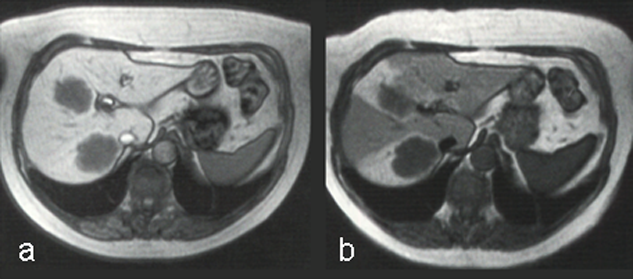

Ferumoxides, or super-paramagnetic iron oxides, are negative enhancers taken up by the normal liver, which contains reticuloendothelial cells, but not by lesions that lack reticuloendothelial cells (Figure 13-15) [⇒ Paley; cf. iron oxides].

Figure 13-15:

Example of a negative liver contrast agent (ferumoxide). This particulate agent is taken up by en­do­the­lial and Kupffer's cells. They darken the liver tissue due to their effective shortening of the T2 relaxation time.

T2-weighted GRE: (a) precontrast; (b) postcontrast. The liver metastases are well delineated on the post-contrast image; with this agent, the normal liver tissue becomes black.